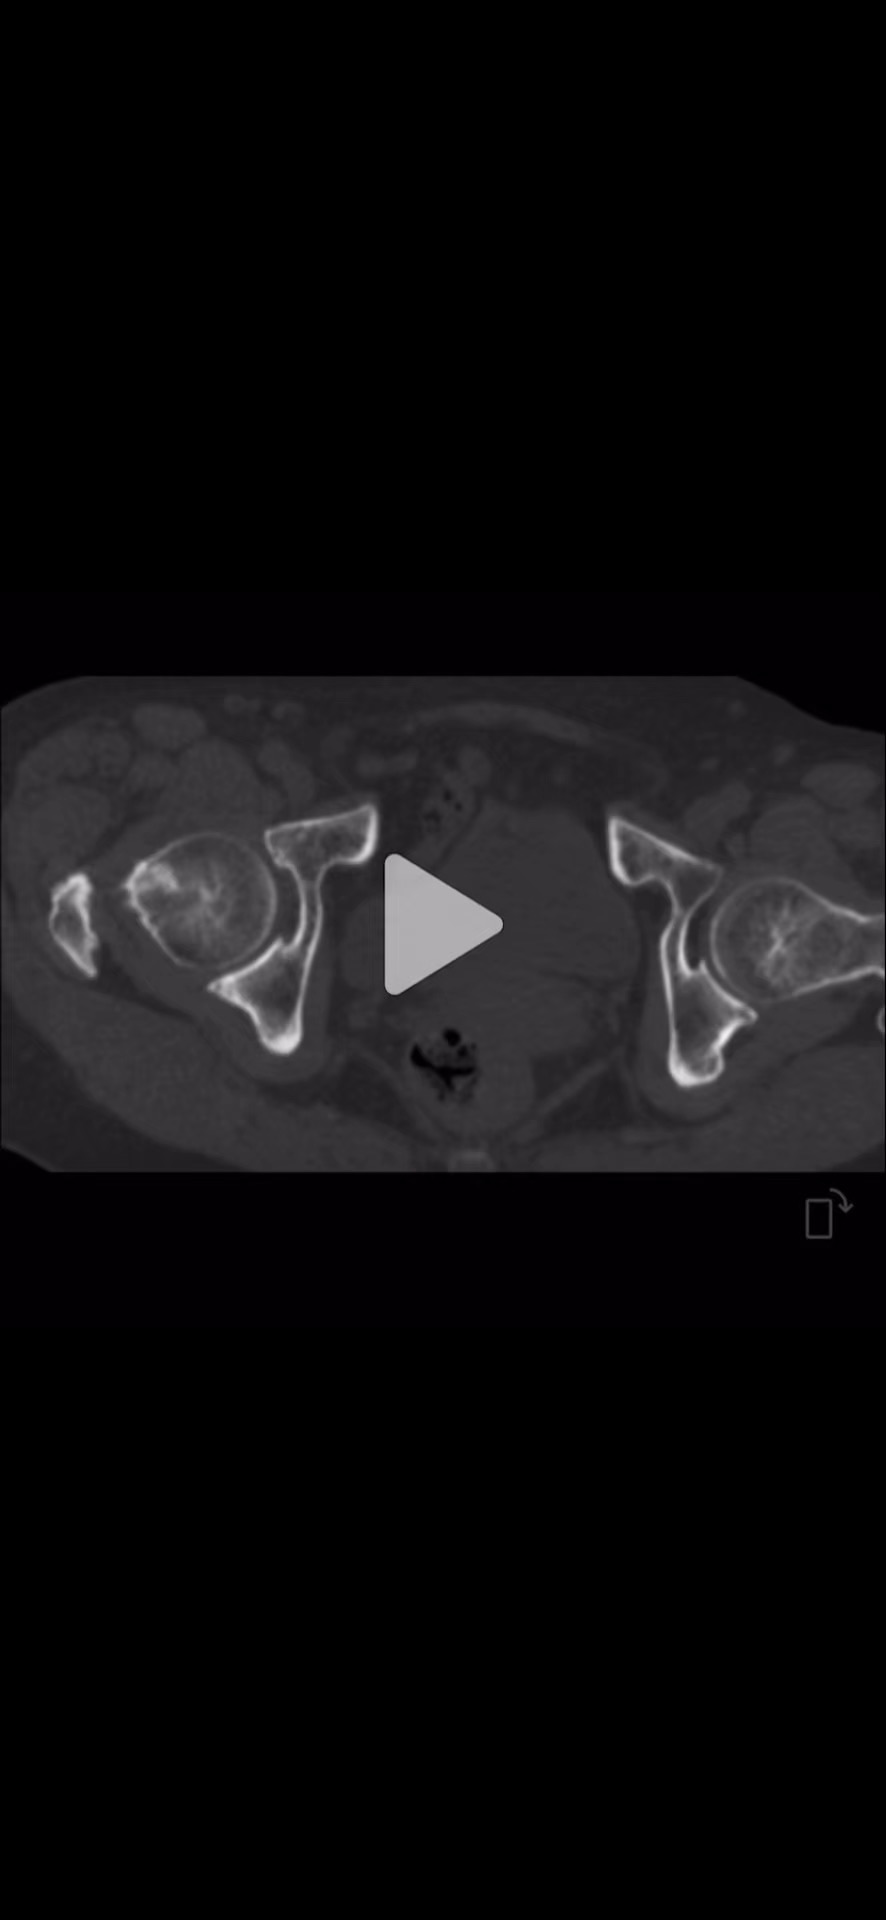

CT: